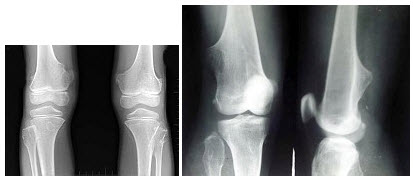

300、单项选择题

男,14岁,偶然发现双膝部肿块1天,双膝关节摄片如图,最可能的诊断是()